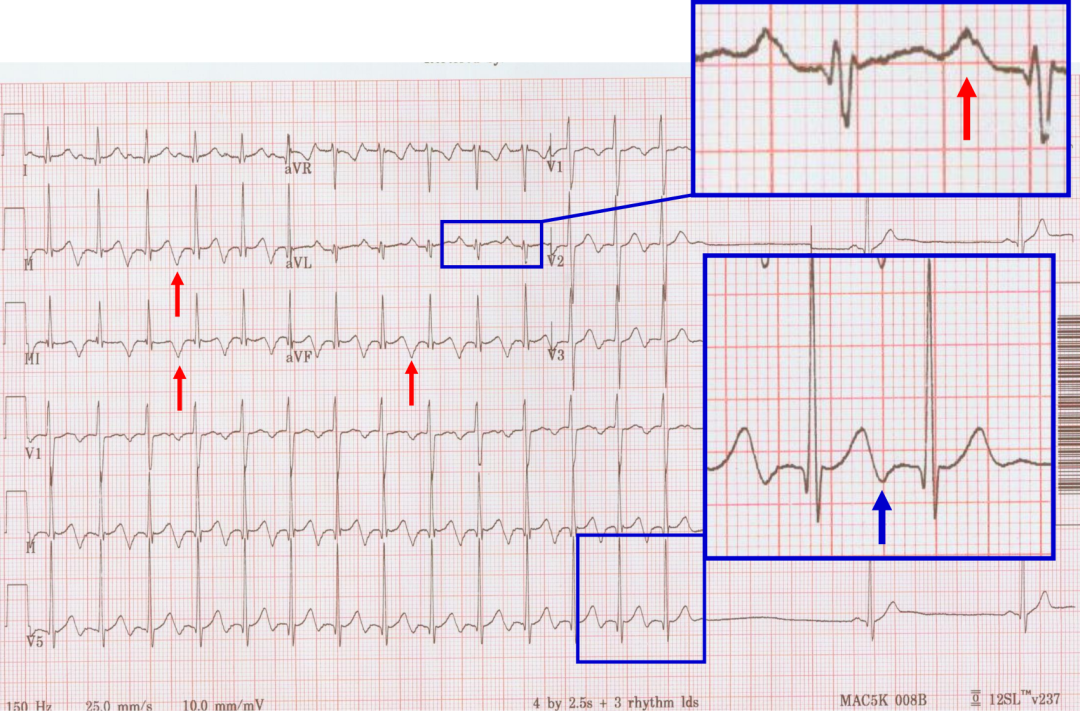

案例三

p心电图功能怎么开通异位起源P波的心电图定位_https://www.jmylbn.com_新闻资讯_第15张

p心电图功能怎么开通异位起源P波的心电图定位_https://www.jmylbn.com_新闻资讯_第16张